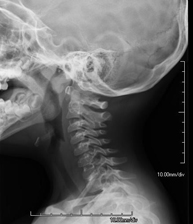

- Cervical spine X-ray

This technique uses X-ray rendered imaging for examining the cervical spine. Indicated for: trauma, cervical contracture, joint pain.

This technique uses X-ray rendered imaging for examining the cervical spine. Indicated for: trauma, cervical pain.